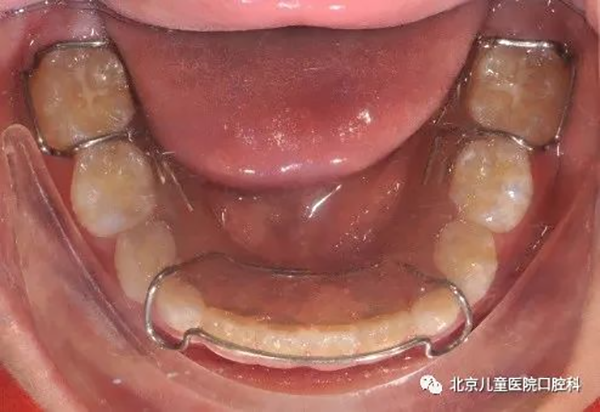

多为粘接于牙齿舌面的舌侧丝保持器。常用于下切牙拥挤解除后需要永久保持的成年患者。